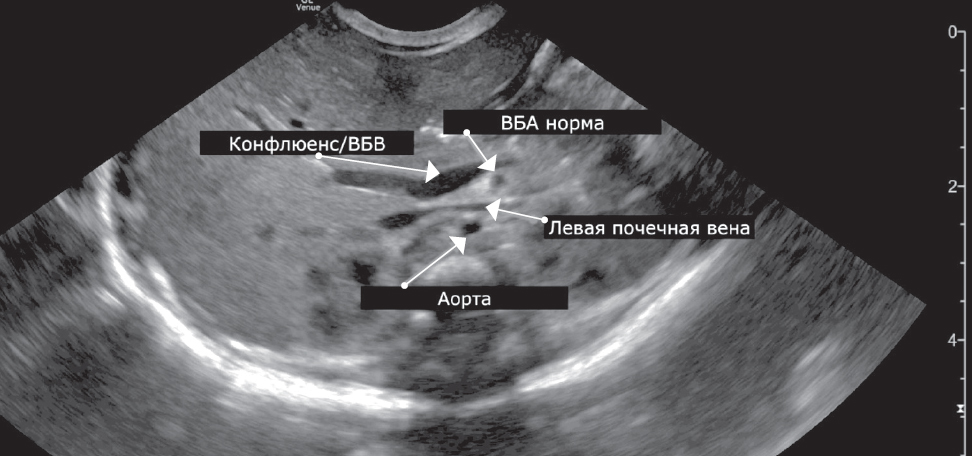

У двоих детей отсутствовали ультразвуковые признаки, указывавшие на мальротацию. В одном случае взаиморасположение мезентериальных сосудов представлялось типичным (рис. 4), во втором получена информация только о наличии жидкости и расширенных петлях кишечника.

Рис. 4. Нормальное расположение мезентериальных сосудов у новорожденного, В-режим

Fig. 4. Normal location of mesenteric vessels in a newborn, B-mode